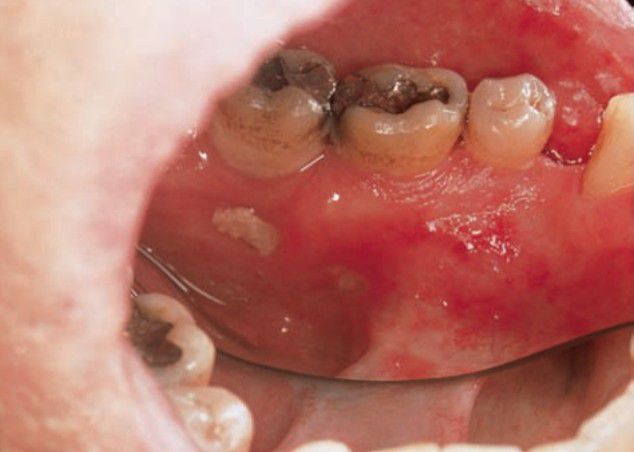

Post radiation osteoradionecrosis

Because osteonecrosis is a danger that is always present after radiation, tooth extractions should be avoided after therapy.